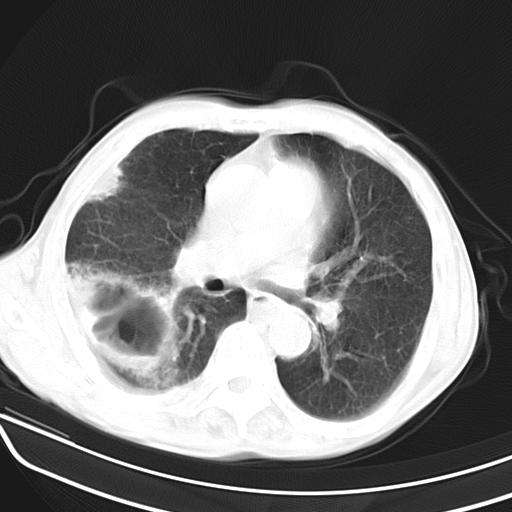

抗炎治疗10天后复查

抗炎治疗10天后复查:右上肺模糊阴影明显减少。